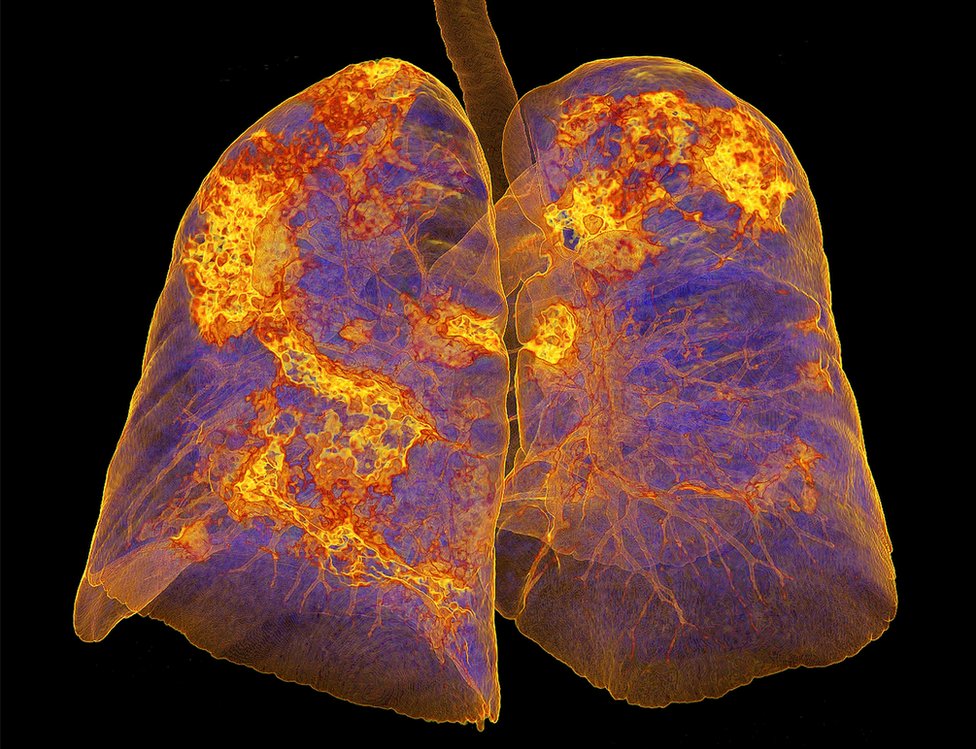

Profesor Kris Brajtling, sa Univerziteta u Lesteru i glavni istraživač za PHOSP-Kovid projekat koji prati oporavak ljudi, smatra da ljudi koji su dobili upalu pluća možda imaju problema zbog oštećenja na plućima.

Infekcija bi mogla i da izmeni kako funkcionišu organi ljudi. Ovo je najočiglednije kod pluća ukoliko na njima ostanu ožiljci – dugoročni problemi viđeni su i posle infekcije Sarsa ili Mersa, a oba su tipovi korona virusa.